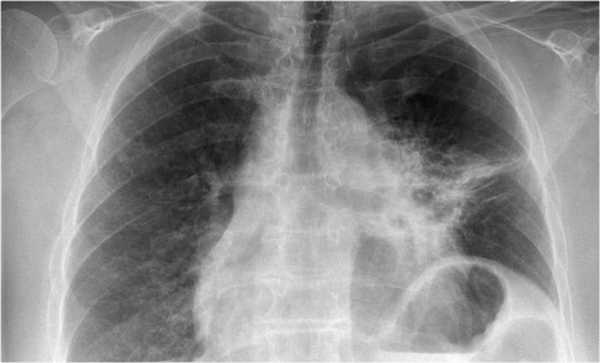

На рентгенограмме органов грудной клетки определяется тотальный ателектаз правого легкого со смещением средостения вправо. На втором снимке представлен тот же пациент, но после лечения. Легкое воздушное и положение средостения в норме. Распространенной причиной тотального ателектаза является неправильно установленная вентиляционная трубка, которая расположена слишком низко и тем самым обтурирует главный бронх.

На ниже представленном снимке представлен пациент с тяжелой бронхопневмонией и тотальным ателектазом. Причиной ателектаза явилось обтурация бронха слизью. После отсасывания мокроты аэрация левого легкого была восстановлена.